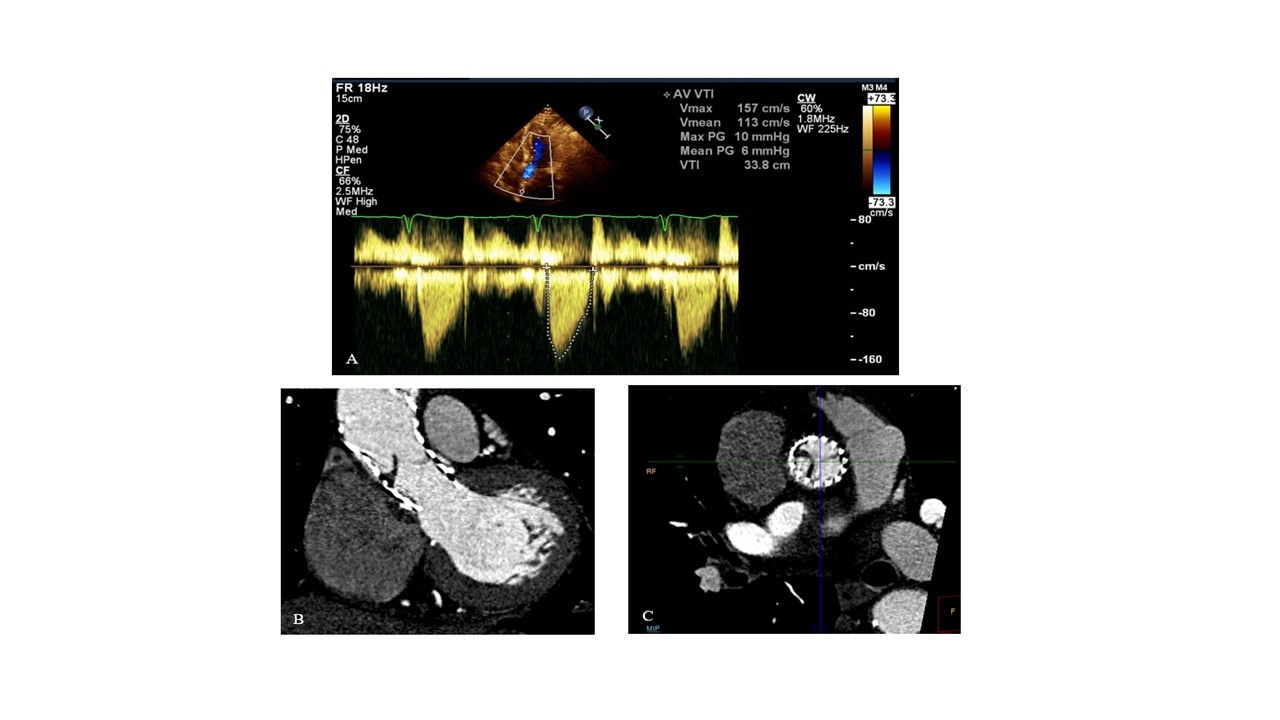

Results: Of 19 consecutive patients, 3 were found to have high-grade leaflet thrombosis based on CCT results. The SVM algorithm effectively classified heart sounds into "normal" and "thrombotic", with a sensitivity of 100% and specificity of 97.2%. Following anticoagulation therapy, all 3 patients showed no signs of leaflet thrombosis on follow-up CCT scans and were also classified as "normal" by the algorithm. Notably, at the time of leaflet thrombosis, Doppler echocardiographies showed normal pressure gradients across the affected valves.